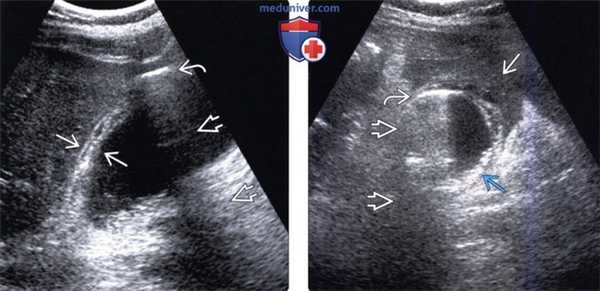

(Слева) На сонограмме у мужчины 79 лет с жалобами на боль в правом подреберье определяется утолщение стенки желчного пузыря, в передней стенке визуализируется эхогенный участок вытянутой формы. Обратите внимание на «грязную» заднюю акустическую тень - сонографический артефакт, характерный для газа.

(Справа) На поперечной сонограмме у этого же пациента определяются интрамуральные включения газа дающие «грязную» акустическую тень. Обратите внимание на инфильтрированный сальник, вплотную прилежащий к желчному пузырю, и слой небольших камней. При патоморфологическом исследовании подтвердился гангренозный холецистит.